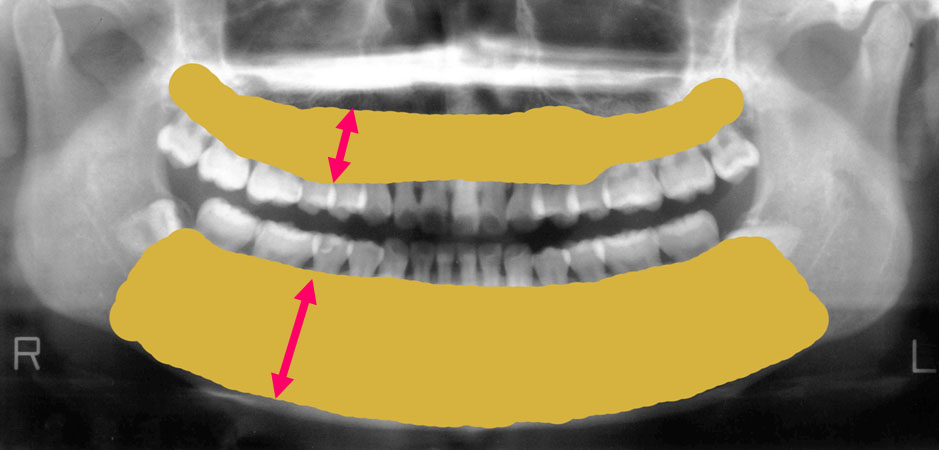

歯を支えている骨部分が今はこれだけの量があります。

しかし骨が少なくなるとこんな風になってしまうのです。